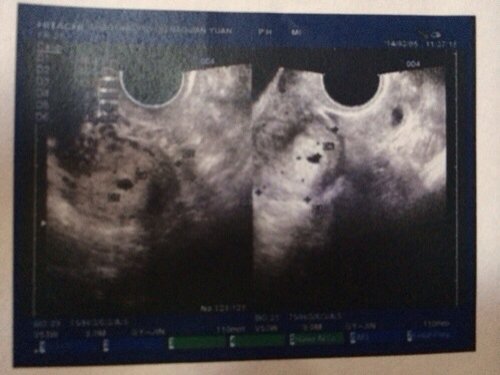

我3月1号去检查抽血检查了孕酮和HCG和叶酸,HCg就900多,3号再去检查HCG值就1200左右,5号今天检查HCG就1440左右,医生怕是宫外孕给我检查阴超,但是医生下班了来不及问这张阴超报告了,请问阴超报告怎么说?

病情分析: 根据你所描述的情况,你的B超报告的是怀孕的,但是没有见到胎芽,及泰兴管博动, 指导意见: 你好,如果你现在是怀孕40天,就属于正常的,否则你的孕囊没有发育好的,超过45天应该看到胎芽的。祝健康。